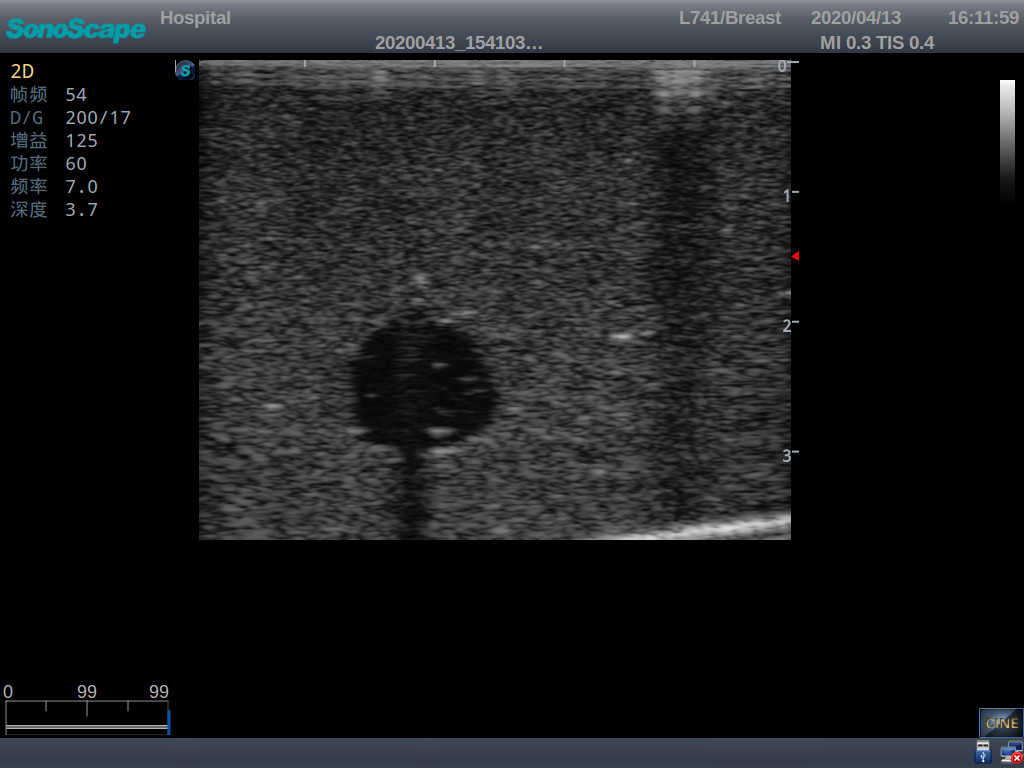

Wearable Breast Ultrasound Examination Model

Model TYE1568.1

The Wearable Breast Ultrasound Examination Model allows users to develop and practice the skills necessary to gain proficiency in breast palpation, using ultrasound for normal and abnormal imaging and biopsy. It simulates adult female breasts with realistic size and appearance.

2)  Each model contains 8 space-occupying lesions of varying sizes, different in touch, elasticity and ultrasonogram

4) Biomimetic material allowing users to see clear and real normal tissues and space-occupying lesions that are hyperechoic, hypoechoic and isoechoic as they would see in the clinical environment